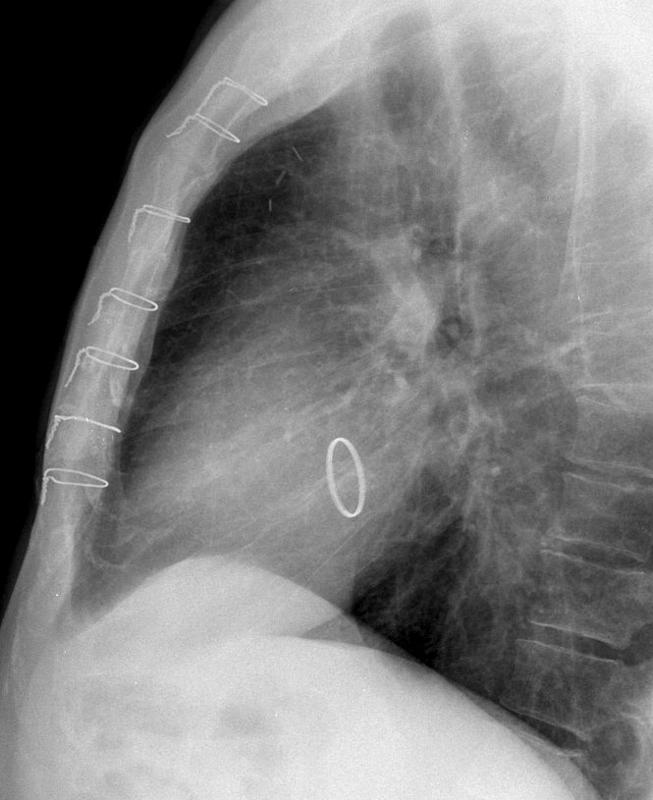

Mitral Valve Disease

Mitral annuloplasty Lat